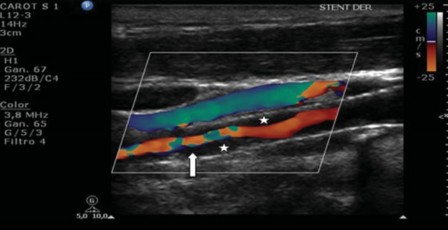

En modo color se debe documentar la permeabilidad del stent, la superficie del mismo y de la pared adyacente. Es preciso objetivar la existencia de zonas de aliasing color. Eso sucede debido a una pérdida dela laminaridad del flujo o bien a la existencia de zonas de turbulencia como consecuencia de una reducción de la luz vascular y, por lo tanto, es un hallazgo de importancia, ya que sería el sitio de interés para evaluar con el Doppler espectral en busca de estenosis (►Fig. 6). Frecuentemente, existen estenosis residuales de las arterias carótidas externas, secundarias al implante de la prótesis, sin implicancias patológicas relevantes.

Ecografía Doppler color (EDC) con ocupación de un tejido hipoecóico que prolifera hacia la luz (hiperplasia neointimal), con reducción de la luz vascular (estrella). El mapa color muestra el lumen disminuido con una zona de aliasing color (flecha).